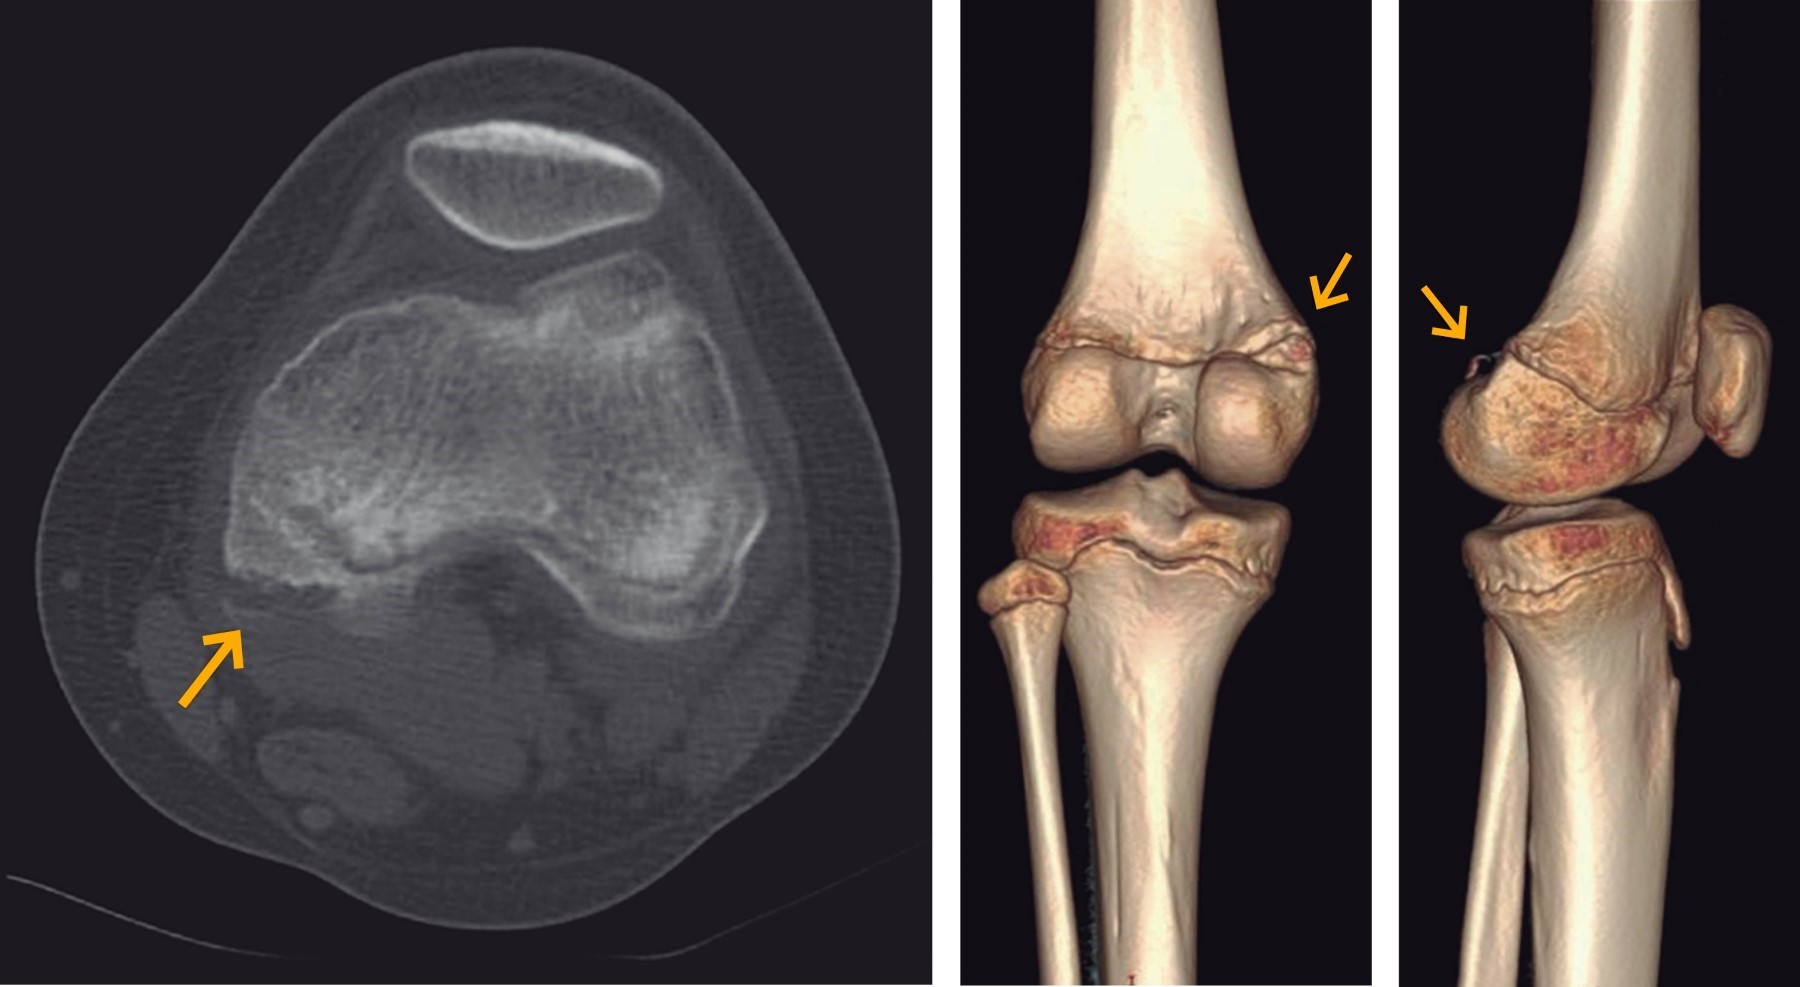

A 12-year-old female gymnast presented with acute pain on the back of her left knee sustained during training. Initial radiographs were unremarkable (Figure 1), prompting further imaging for a definitive diagnosis. A computed tomography (CT-scan) revealed the bone component of the lesion and the degree of displacement (Figure 2). Magnetic resonance imaging demonstrated an avulsion fracture at the posteromedial aspect of the femur arising from the origin of the tendon of the medial gastrocnemius muscle (Figure 3). There were no associated injuries or tears to the medial head of the gastrocnemius muscle.

Given the rarity of this condition, maintaining a high index of suspicion is paramount, particularly in patients presenting with pain localized to the popliteal fossa during hyperextension, difficulty with knee flexion, and minimal effusion. In high-energy trauma scenarios involving valgus and hyperextension forces, the possibility of posteromedial instability should prompt further investigation. X-rays alone may fail to detect this condition, necessitating the use of advanced imaging modalities. Magnetic resonance imaging, in particular, offers a comprehensive assessment by differentiating between potential diagnoses, identifying associated ligament or meniscal injuries, and detecting osteochondral fractures.15,16 Although CT lacks the sensitivity for soft tissue evaluation, it remains crucial for assessing the avulsion fragment's characteristics and planning surgical intervention, when necessary, especially through 3D reconstruction.17

Figure 2